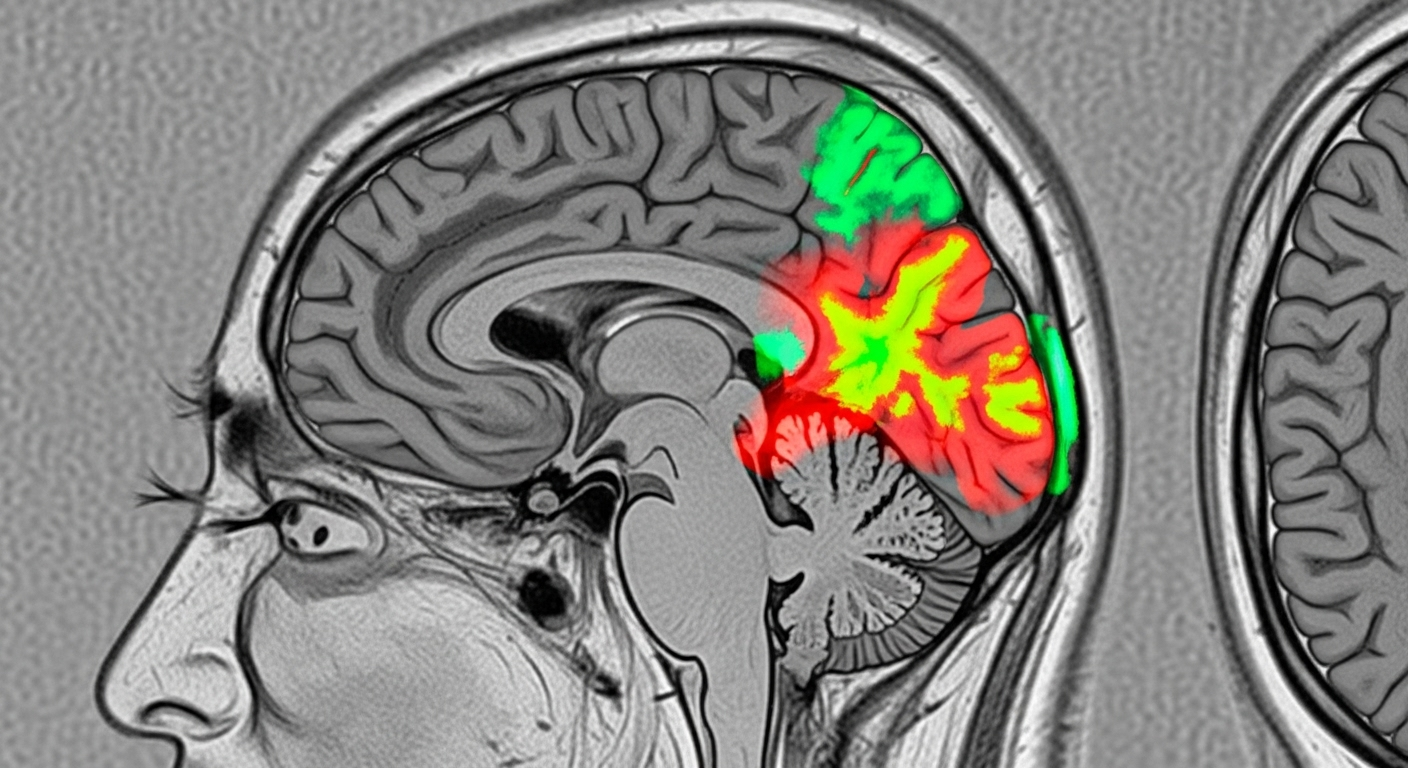

Des chercheurs de l’Institut Karolinska en Suède ont mené une étude d’envergure. Ils ont examiné les habitudes de sommeil et les scanners cérébraux (IRM) de plus de 27 000 adultes britanniques âgés de 40 à 70 ans. Leur découverte est stupéfiante : les personnes qui déclaraient mal dormir avaient un cerveau qui, littéralement, ‘avait l’air plus vieux’ que leur âge réel. Pour arriver à cette conclusion, ils ont utilisé une intelligence artificielle pour analyser plus de 1 000 marqueurs différents sur les images IRM.

L’IA a d’abord « appris’ à quoi ressemblait un cerveau normal » pour un âge donné. Ensuite, les chercheurs l’ont appliquée à tous les participants. Le résultat est précis et inquiétant : pour chaque point de qualité de sommeil en moins (sur une échelle définie par l’étude), le cerveau avait vieilli d’environ six mois. Les personnes qui dormaient le plus mal avaient un cerveau qui paraissait un an plus vieux que leur âge chronologique. C’est un peu comme si votre cerveau prenait des rides à cause de vos mauvaises nuits.